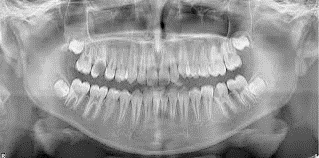

You may need a wisdom teeth extraction at some point in your life. It is rare for a person to have enough room for all of their wisdom teeth, and as a result, they tend to grow in impacted. This can be uncomfortable, push your other teeth forward, and create a space for food to become trapped; it can also increase your risk of infection and decay. This is why we often recommend that our patients have their wisdom teeth removed. When you schedule an appointment with Durango Dentistry, we can examine you, take X-rays, and let you know if and when you should schedule an extraction procedure. You can reach us by calling (970) 259-1646.

At Durango Dentistry, we understand that each of our patients is unique and so are their teeth. Whether or not you need to have your wisdom teeth removed by a dentist, will really depend on the size of your palate. If you have plenty of room for all of your teeth and your third molars, they can stay in place. There is no point in removing something that grows in straight and is healthy. However, any tooth that grows in impacted needs to be removed because it is posing a direct threat to your other teeth and roots in addition to being a target for infections. The best way to find out if your wisdom teeth should be removed is to call (970) 259-1646 and schedule an appointment with our Durango dentist office. We can make a recommendation and answer any other questions you have about the procedure itself.